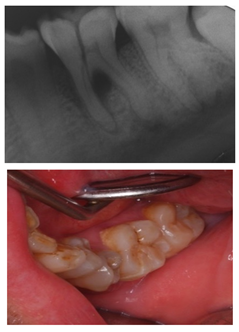

3.6. Clinical Scenario #6

The first question (clinical scenario 6a) consisted of two options: “root canal treatment” and “extraction”, and students were required to select which of the proposed options would be most adequate for the proposed case. In this case, the correct alternative was “root canal treatment”, which was selected by 56.1% of the students.

The second question (clinical scenario 6b) was asked to those who selected “root canal treatment” as the treatment for the proposed case, and required them to order different alternatives for the restoration after root canal treatment. The “direct restoration with resin composite” was selected by 78.3% of the students, which was the correct option. Additionally, 13% of the students would additionally place a post and a crown. The least repeated restoration among the surveyed students was “incrustation” (8.7%).

The third question (clinical scenario 6c) should only be answered by those who selected “extraction” as the treatment for the proposed case, and required them to order different alternatives for the tooth replacement. The options “deferred implant” or “fixed prosthesis” were the most prevalent (44.4%). To a lesser extent (11.2%), students opted for the placement of an “immediate implant”. The placement of a “deferred implant” was considered as correct (Figure 1).

Upon carious lesions with a greater extension, the therapeutic approach becomes varied depending on the extent of the lesion. When the pulp is reversibly affected, or an accidental pulp exposure is produced when removing affected tissue from deep carious lesions, the preservation of pulp vitality is preferable [31,37]. A direct pulp capping is indicated in cases where an asymptomatic pulp exposure with a controllable bleeding is produced, and the tooth is restorable. Pulpotomy is reserved for pulp exposures of greater size (>1 mm) and whose bleeding can be controlled within a period of 1–2 min [21]. The results from our study show that the surveyed students majorly coincide with the current recommendations for the treatment of the vital pulp. The participants would perform a pulp capping on clinical scenarios 2 and 4. However, the majority of them would then place a temporary restoration (i.e., two-stage selective caries removal), while available evidence supports one-stage selective removal procedure [20,38].

When the inflammation of the pulp is accompanied by periapical pathology, a more invasive operatory approach is required. In the case of suppurative chronic periapical periodontitis the ideal approach would be root canal treatment [21]. This situation was presented in clinical scenario 6a, where 56.1% of the surveyed students opted for root canal treatment. Those who selected this treatment option then would restore the tooth with a resin composite (clinical scenario 6b), which was the answer considered as correct. For the treatment of small or medium-sized cavities, where there is enough dental structure to retain a restoration, it would be the most suitable option [29]. Manocci et al. concluded that the outcome of a direct restoration at 3 years of follow-up was the same as the obtained by placing a crown [39].

Approximately 44% of the surveyed students answered that an extraction would be the most suitable option for clinical scenario 6a, which would imply a more aggressive and expensive treatment for the patient if a prosthetic replacement of the tooth with an implant is planned (as answered by 44,4% of the participants in clinical scenario 6c). The investigators proposed the placement of a deferred implant as the most suitable option for the replacement of the tooth if opting for its extraction, since the replacement of a single tooth implies less removal of tooth structure than a fixed prosthesis. Currently, deciding between an immediate or deferred implant is a controversial matter, since there is a great variability among studies in the field, which should be interpreted with caution [40]. The investigators opted for the deferred implant, since the case presented an infectious process which involved the osseous tissue, which could hinder the prognosis of an immediate implant.